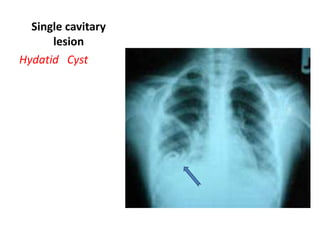

Single cavitary

lesion

Hydatid Cyst

Chest HC